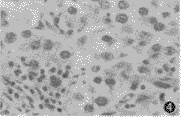

图4 瘤细胞胞浆透亮,胞界清楚,核大深染呈圆形,位于中央,核膜不规则,核分裂多见,瘤细胞排列成小巢状(HE ×400)

病理检查:不规则组织,表面略呈结节状,切面呈实性、灰白色,有出血,局部有黏液样区,质脆。病理诊断:前上纵隔精原细胞瘤(图4)。